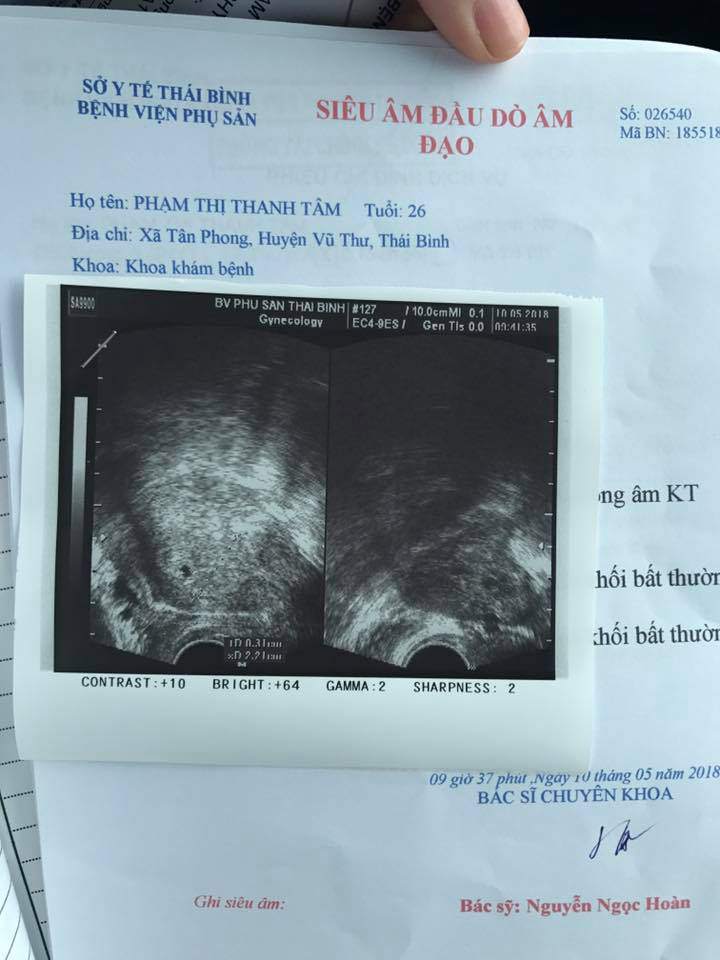

Mẹ nuôi Yến Nhi hiện đã có bầu được khoảng 3 tuần, em bé mới là một phôi thai hơn 3mm và dự sinh đầu năm 2019.

Một ngày của mình bây giờ nói ra thì thật ngại. Mình hiện không ở nhà chồng ở Thái Bình mà đang phải theo bệnh viện tư của bác ruột chồng ở Hà Nội. Mình có hiện tượng đau bụng nhiều và beta giảm nên phải phải nằm yên một chỗ và tiêm dưỡng giữ thai.

Mỗi ngày mình đợi ở phòng khám của bác chờ tiêm 1 mũi giảm nghén, 1 mũi dưỡng thai và 2 mũi giữ thai sau đó tối về nhà nghỉ ngơi. Mình đi lại rất ít, đặc biệt phải kiêng đi lại và leo cầu thang theo yêu cầu bác sĩ vì em bé hơi yếu. Mình đang cố gắng chịu đựng các cơn nghén và mệt mỏi mỗi ngày.